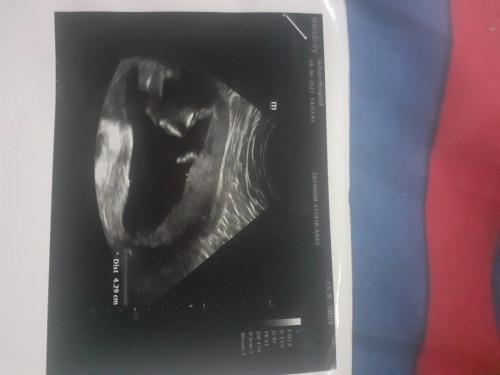

หญิงหรือชายค่ะเเม่ๆช่วยดุไห้หน่อยค่ะ ท้องเเรก

ดูไม่ออกเลยค่ะว่าส่วนไหน หมอได้บอกแม่ไหมคะ 25w เห็นเพศชัดแล้ว นอกจากน้องจะหนีบไว้ไม่ให้เห็น

กี่วีคคะ